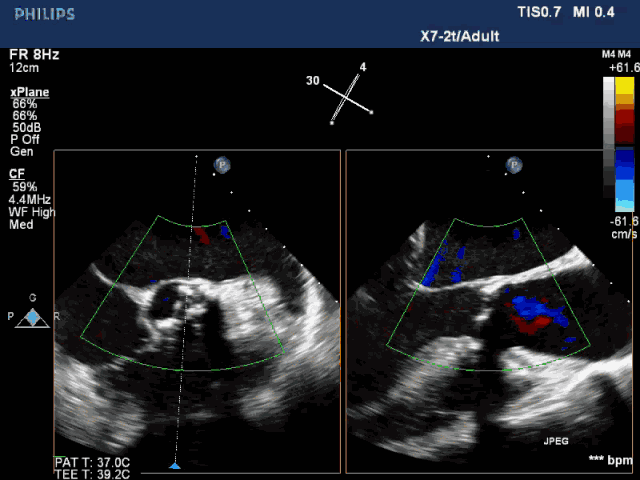

术前心超:

双平面示type 1型二叶瓣

术前全麻状态下LVEF 17.7%